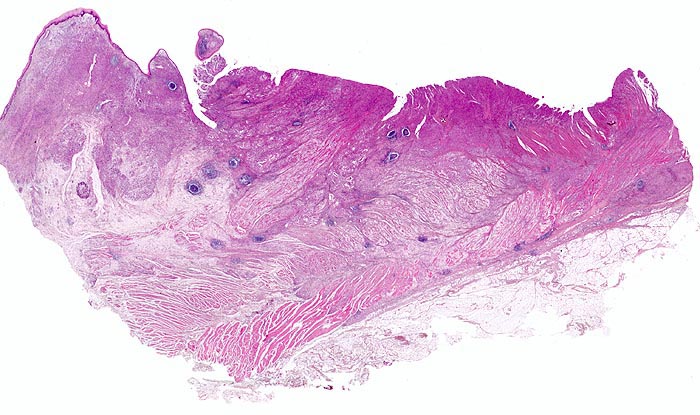

Makroskopisch können nach Borrmann (> 5050) polypoide Tumoren, ulzerierte Tumoren mit Randwall, ulzerierte Tumoren mit Invasion der Magenwand und diffus infiltrierende Tumoren (=Linitis plastica (> 3315)) unterschieden werden.

• Das unscharf begrenzte Karzinom breitet sich diffus in der gesamten Magenwand und in der Ösophaguswand aus bis in des periösophageale und subseröse Fettgewebe.

• Ösophagus mit intaktem plattenepithelialem Schleimhautüberzug.